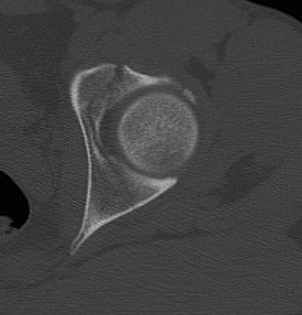

CT

Configuration

1-2 mm sections

CT reconstruction

- remove head to view acetabulum

- beware volume averaging

- used to guide surgery

Diagnose

Loose bodies

Femoral head fractures

Subtle subluxation

Articular steps

Roof arc measurement

B. CT subchondral arc

- 10 mm below subchondral bone of roof

- similar to xray roof arc measurements